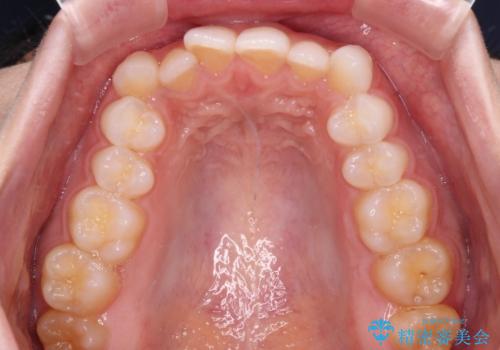

- 前歯のデコボコとクロスバイトを気にして来院された患者様です。

上下ともにデコボコはそれほど強くありませんでしたが、非抜歯では口元が突出した仕上がりとなる可能性があるため、上下左右の第一小臼歯4本を抜歯し、ワイヤー装置での抜歯矯正を行うこととしました

スペースを閉じるために期間を要しましたが、無事に綺麗な口元に仕上げることができました。